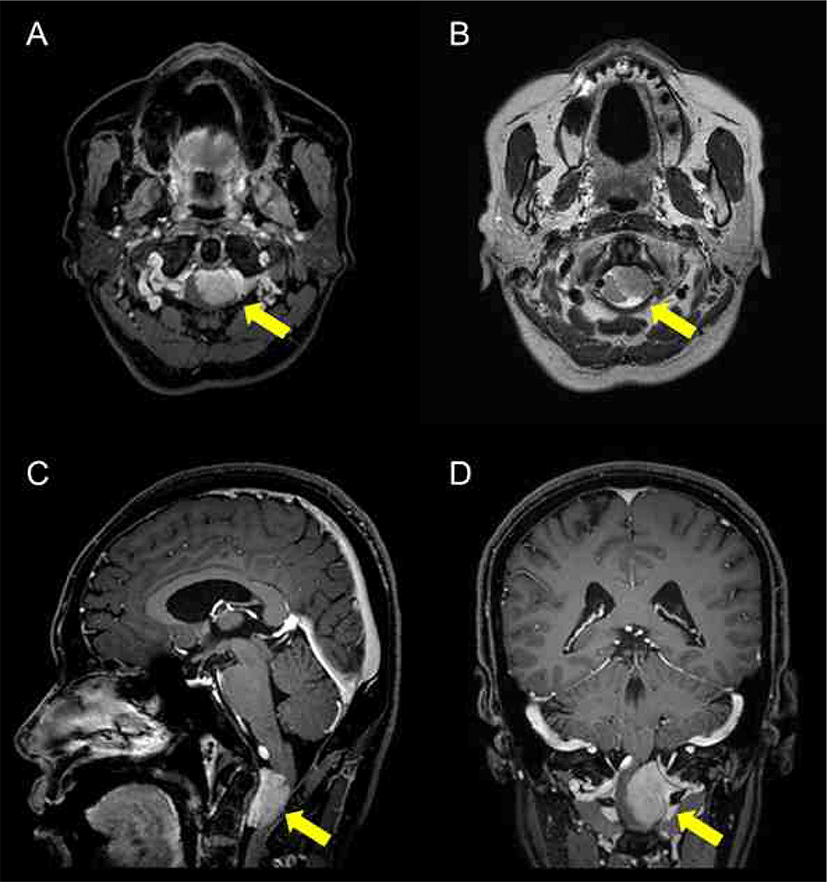

Usefulness of facial MEP monitoring in vestibular schwannoma surgery: a case report

전정신경초종 수술 중 얼굴 운동유발전위 추적감시의 유용성: 증례

J Intraoper Neurophysiol 2020;2(2):109-113.